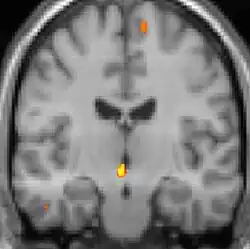

![]() | ![]() | ![]() |

| VBM mostrando diferenças estruturais entre cérebros | ||